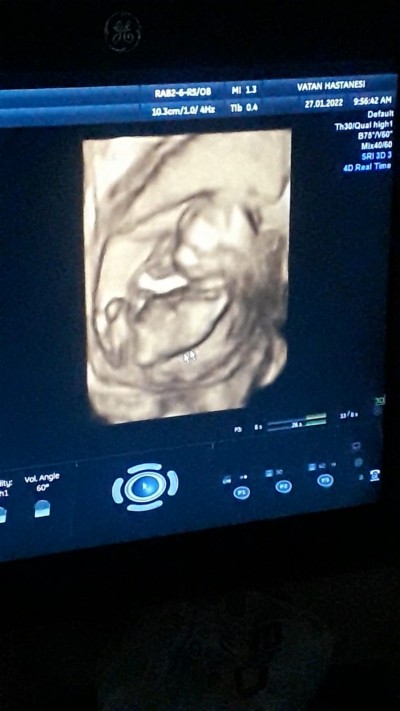

Cinsiyet nedir sizce hanımlar

İlk gebeligim ne olabilir cinsiyet

15+2

Siyah beyaz olan ultrason kağıdı yok mu ben ondan birazcık anlıyorum bunda bacak arası kapalı gibi

Kızımız oluyor.